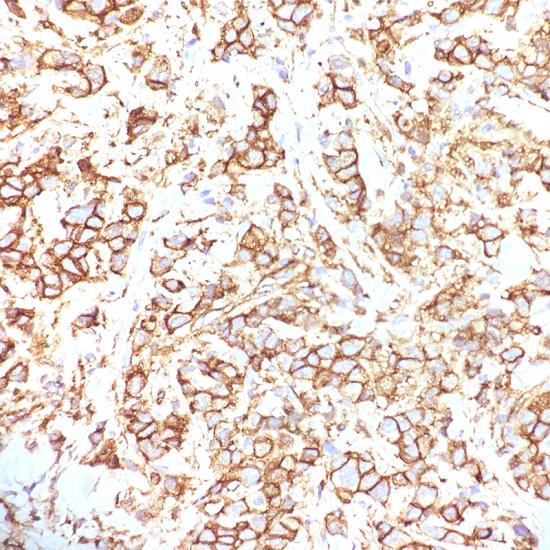

P120 catenin

• 陽性部位:

細(xì)胞漿/細(xì)胞膜

• 陽性對照:

乳腺癌

連接素家族包括α-catenin、β-catenin、γ-catenin和p120-catenin。p120在細(xì)胞膜旁的胞漿中與E-cadherin相連,不與肌動蛋白和α-catenin相連,如果缺乏E-cadherin,將會導(dǎo)致細(xì)胞漿內(nèi)p120的大量累積。在乳腺小葉癌中常顯示p120的大量蓄積,在乳腺導(dǎo)管癌中僅有少量細(xì)胞膜表達(dá),而在細(xì)胞漿內(nèi)沒有p120的蓄積。此抗體可用于乳腺導(dǎo)管和小葉腫瘤的研究。